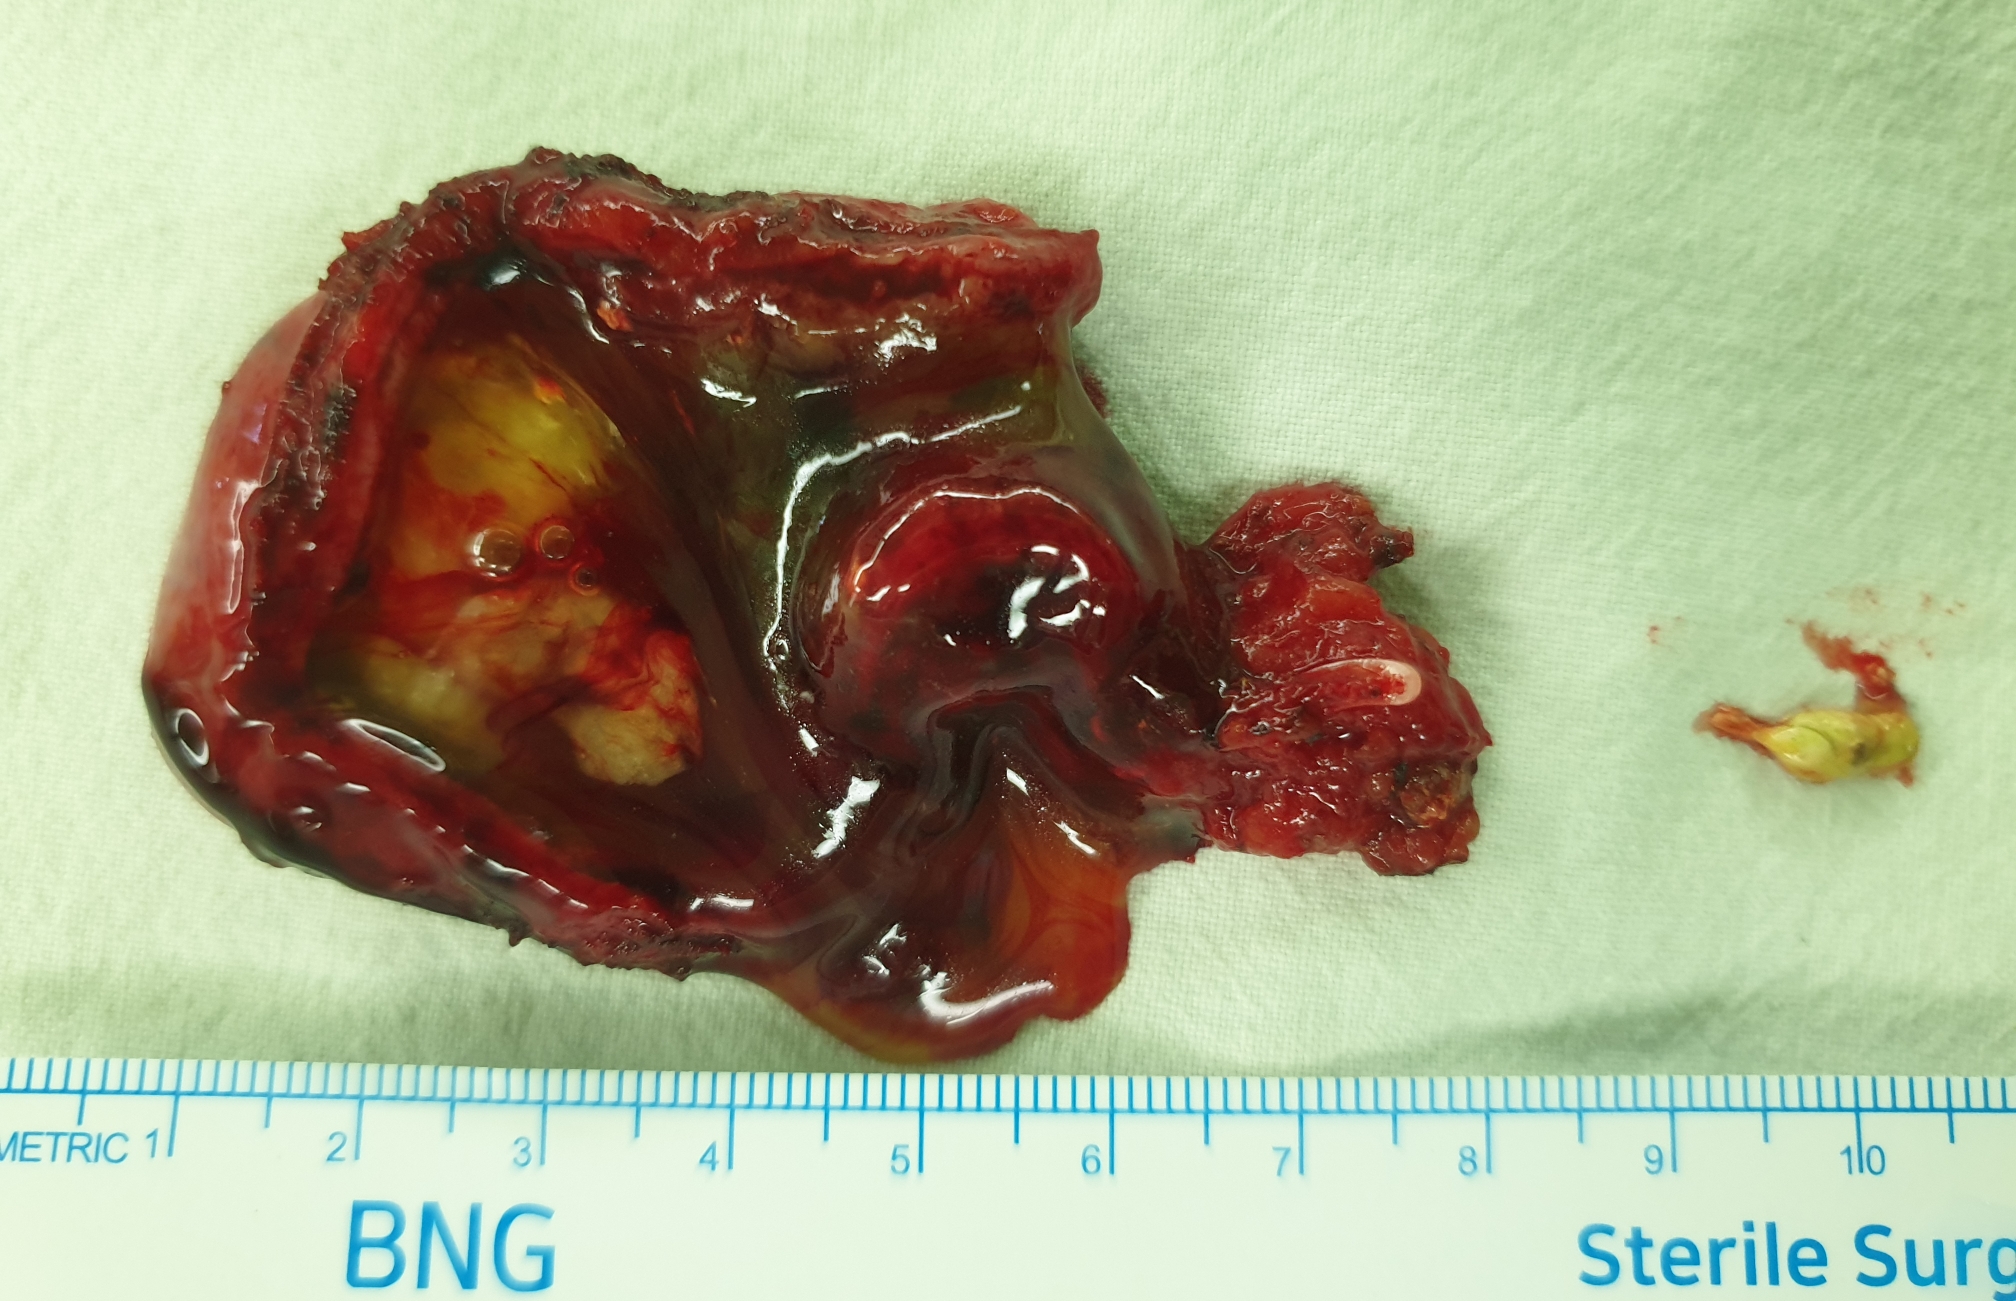

빠른 수술을 원하셔서 방금 복강경 담낭절제술을 시행했습니다.

수술은 30분 걸렸습니다.